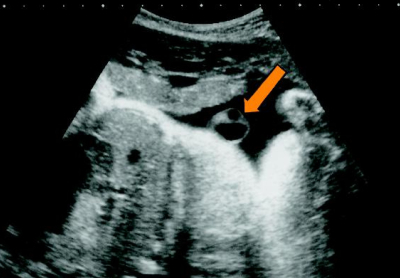

身長160 cm、体重 59 kg。体温 36.6 ℃。脈拍 80/分、整。血圧 120/72 mmHg。内診時の帯下では BTB 試験紙の色の変化はなかった。腹部超音波検査で胎児は頭位で、推定体重は 2,050 g、羊水指数<AFI>は 3.8 cm だった。臍帯断面の超音波像及びノンストレステスト<NST>の結果を別に示す。

矢印=臍帯断面